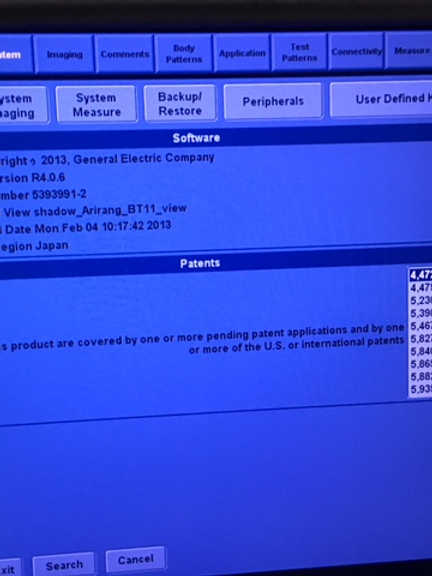

Introduction: Experience cutting-edge imaging technology at an affordable price with the LOGIQ P5 Ultrasound Scanner. Compact, ergonomic, and packed with high-end features, this ultrasound device redefines diagnostic excellence without breaking the bank.

Unrivaled Imaging Capability: From gynaecology/obstetrics to urology, cardiology, and paediatrics, the LOGIQ P5 delivers exceptional 3D/4D imaging across a range of medical specialties. With its advanced features, it stands as the most powerful system in its price range, offering unmatched diagnostic precision and clarity.

Feature-Rich Performance: Enjoy access to premium features typically found on more expensive devices, including CrossXBeam composite imaging, cardiac imaging, and speckle reduction. The LOGIQ P5 sets a new standard for affordability without compromising on performance.